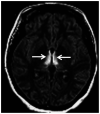

Recent findings: Neurologic complications related to bariatric surgery are predominantly due to nutrient deficiencies. Common early complications include Wernicke encephalopathy due to thiamine deficiency, and late complications include myelopathy or myeloneuropathy due to vitamin B12 or copper deficiency.